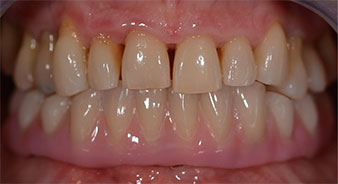

La patiente âgée de 64 ans présente une denture résiduelle des dents 38, 33 et 43 et une prothèse amovible mandibulaire stabilisée par crochets (Fig. 1 et 2).

Fig. 1